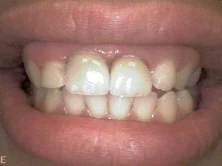

smile.jpg

Cases

Restorations: RCT+Emax crowns

Before